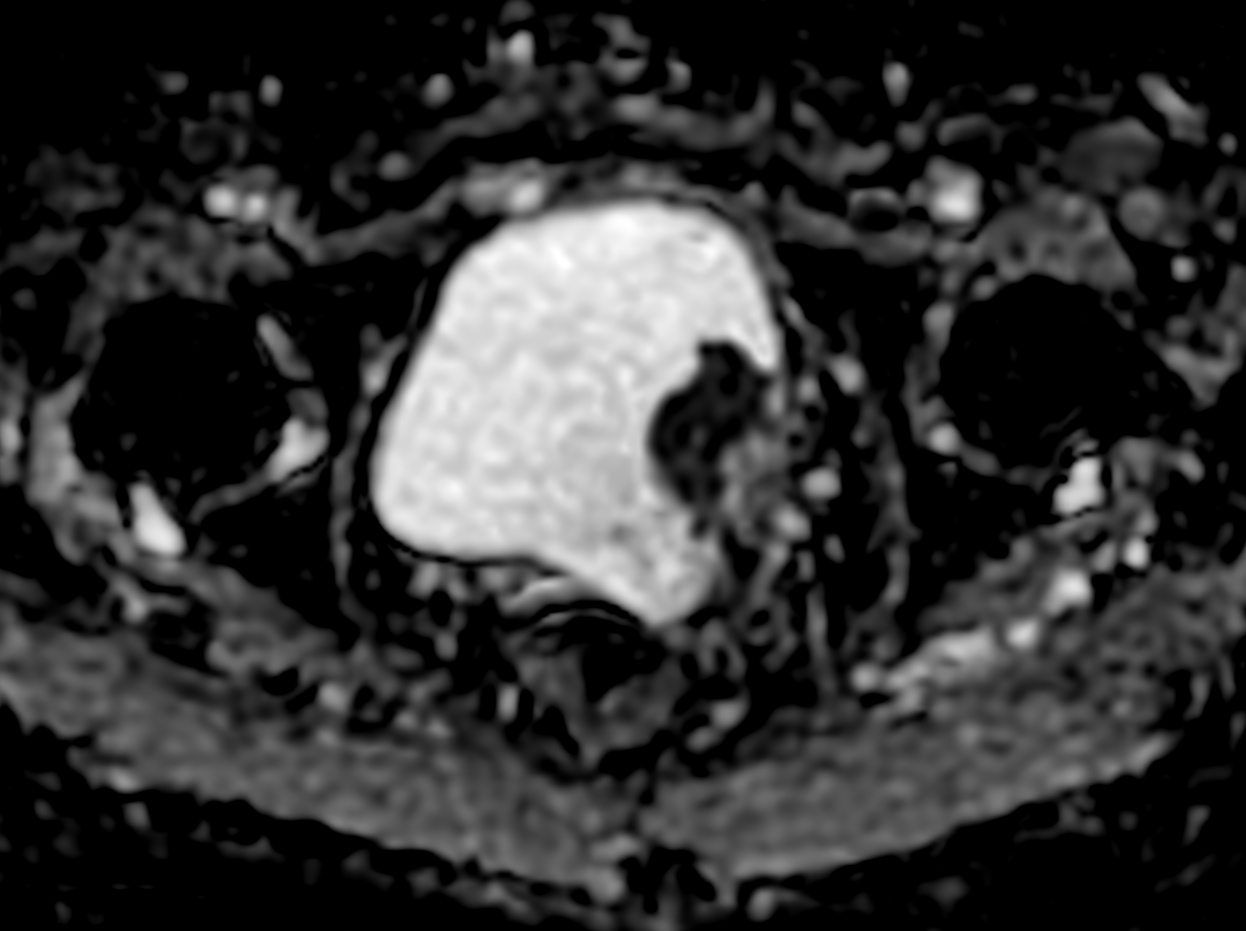

Patient with bladder cancer. The ExamCard includes techniques for motion reduced imaging (MultiVane XD), 3D TSE imaging (PelvisVIEW) allowing for multiple image directions in one single scan, a multi-phase contrast-enhanced sequence (4D FreeBreathing) to improve imaging confidence and Compressed SENSE to accelerate the entire exam.

DWI b1200

DWI b1200 (ADC)